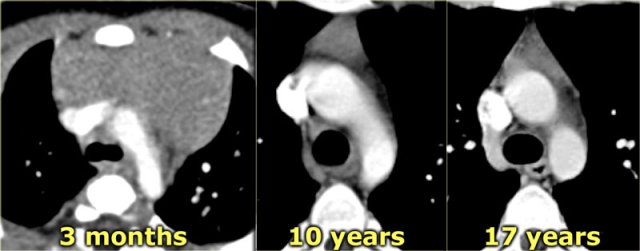

Thymic hyperplasia Thymic hyperplasia

Thymic hyperplasia

Thymic hyperplasia is another cause of thymic enlargement. In childhood, thymic hyperplasia is most often 'rebound' hyperplasia associated with chemotherapy, particularly therapy with corticosteroids.

Rebound hyperplasia may be observed during the course of chemotherapy or after therapy completion and occurs 3 to 10 months after the start of chemotherapy.

On CT, hyperplasia appears as diffuse enlargement of the thymus, with preservation of the normal triangular shape.

The definition of thymic hyperplasia is a > 50 % increase in volume of the thymus. CT, MRI of PET cannot differentiate rebound hyperplasia from infiltration of the thymus by tumor.

The absence of other active disease and a gradual decrease in thymus size on serial CT's supports the diagnosis of rebound hyperplasia.

The thymus usually returns to its normal size in 3 to 6 months.